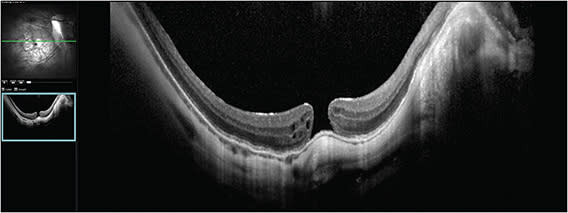

Dr. Vajzovic: This is a case of recurrent myopic macular hole in a 48-year-old male patient who had a long-standing history of degenerative myopia. His axial length is 34 mm. Interestingly, he had prophylactic macular buckle surgery performed in both eyes in 2012. Before seeing this patient, I didn’t know macular buckles were performed prophylactically in the United States. He had cataract extraction done, and unfortunately he developed myopic macular hole in the right eye. He underwent primary vitrectomy and membrane peeling with shorter-acting gas in 2016. At that time, the hole closed and his vision was back to 20/20. Then the hole reopened a few months later and he underwent secondary vitrectomy and membrane peel. The hole closed again, then 3 years later it reopened and he underwent surgery again with longer-acting gas. Each time a membrane peeling was performed. This time, the hole did not close. On the optical coherence tomography (OCT) taken at presentation, the macular hole size was 200 µm, which is not huge, and edges were everted with cystic changes, which is a good prognostic sign (Figure 1). At this point, he was already on drops and he was tried on topical therapy after the last procedure. However, looking at this, topical therapy alone likely will not be the fix. His visual acuity is 20/64, which is remarkably good after all the prior macular hole surgeries. I was really intrigued by that. I questioned whether that macular buckle was actually well positioned and doing him any good or if it had something to do with the hole reopening. The OCT did not show thick epiretinal membranes or anything more concerning than that. There is quite a myopic fundus with peripapillary atrophy and staphyloma as well.

I was able to reach the macula with combination of Flex Loop and myopic forceps. I didn’t think it was helpful to use ILM as a flap because it was not quite continuous. I extended the peel even more broadly to the arcades and little past those. I did a fluid–air exchange and filled the eye with gas. I choose gas for these cases over silicone oil because I have had patients who are very myopic and silicone oil does not quite tamponade, and with the staphyloma, there might be a pocket of fluid in between that silicone oil and the retina. I’ve also found that longer-acting gas and 1 week of positioning has helped closure of myopic holes. For this patient, the OCT image taken 1 week after surgery through a gas-filled eye showed that the hole had closed (Figure 2).